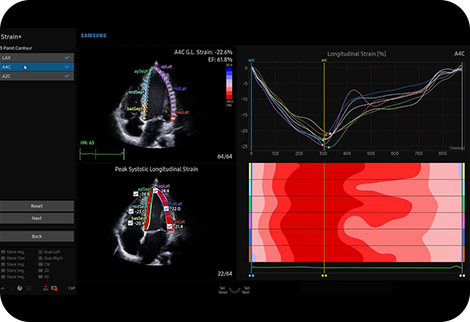

Kvantifikace pohybu stěny levé komory |

Strain+ je kvantitativní nástroj pro měření globálního a lokálního pohybu stěny levé komory (LK). V funkci Strain+ jsou zobrazeny tři standardní pohledy na LK a souhrn ve vzoru terče na jedné obrazovce pro snadné a rychlé posouzení funkce LK.